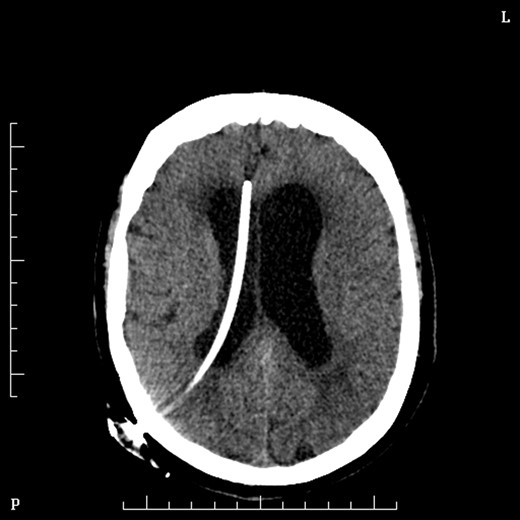

Two days later she underwent an operation to remove the lesion. She was positioned prone in mayfield head clamp and skull pins. A suboccipital craniotomy was performed to gain exposure and the lesion was removed using stereotaxy and operating microscope. Frozen section at the time of surgery was suggestive of Choroid Plexus Papilloma and indeed the formal histopathology confirmed this some days later. Day 1 post-operatively Mrs MM. had cranial nerve VI and VII palsies and was slow to recover. On post-operative day 2 she had a sudden drop on GCS and urgent CT brain demonstrated obstructive hydrocephalus and she underwent insertion of VP shunt (Fig. 4).